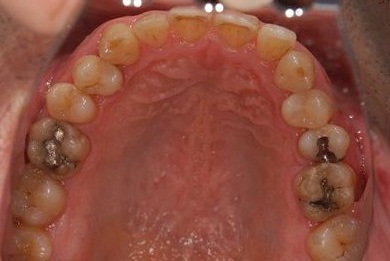

| 性別/年齢 | 男性 / 37歳 | ||||||||||||||||||||||||||||||||

| 主訴 | 前歯(2本)の欠けの治療 | ||||||||||||||||||||||||||||||||

| 治療方針 | 右下欠損部分をインプラント治療にて、機能的・審美的回復を行う。 | ||||||||||||||||||||||||||||||||

| 治療内容 | インプラント1本、メタルボンドセラミッククラウン1本 | ||||||||||||||||||||||||||||||||

| 総治療費 | 252,000円 | ||||||||||||||||||||||||||||||||

| 治療期間 | 7ヶ月 |